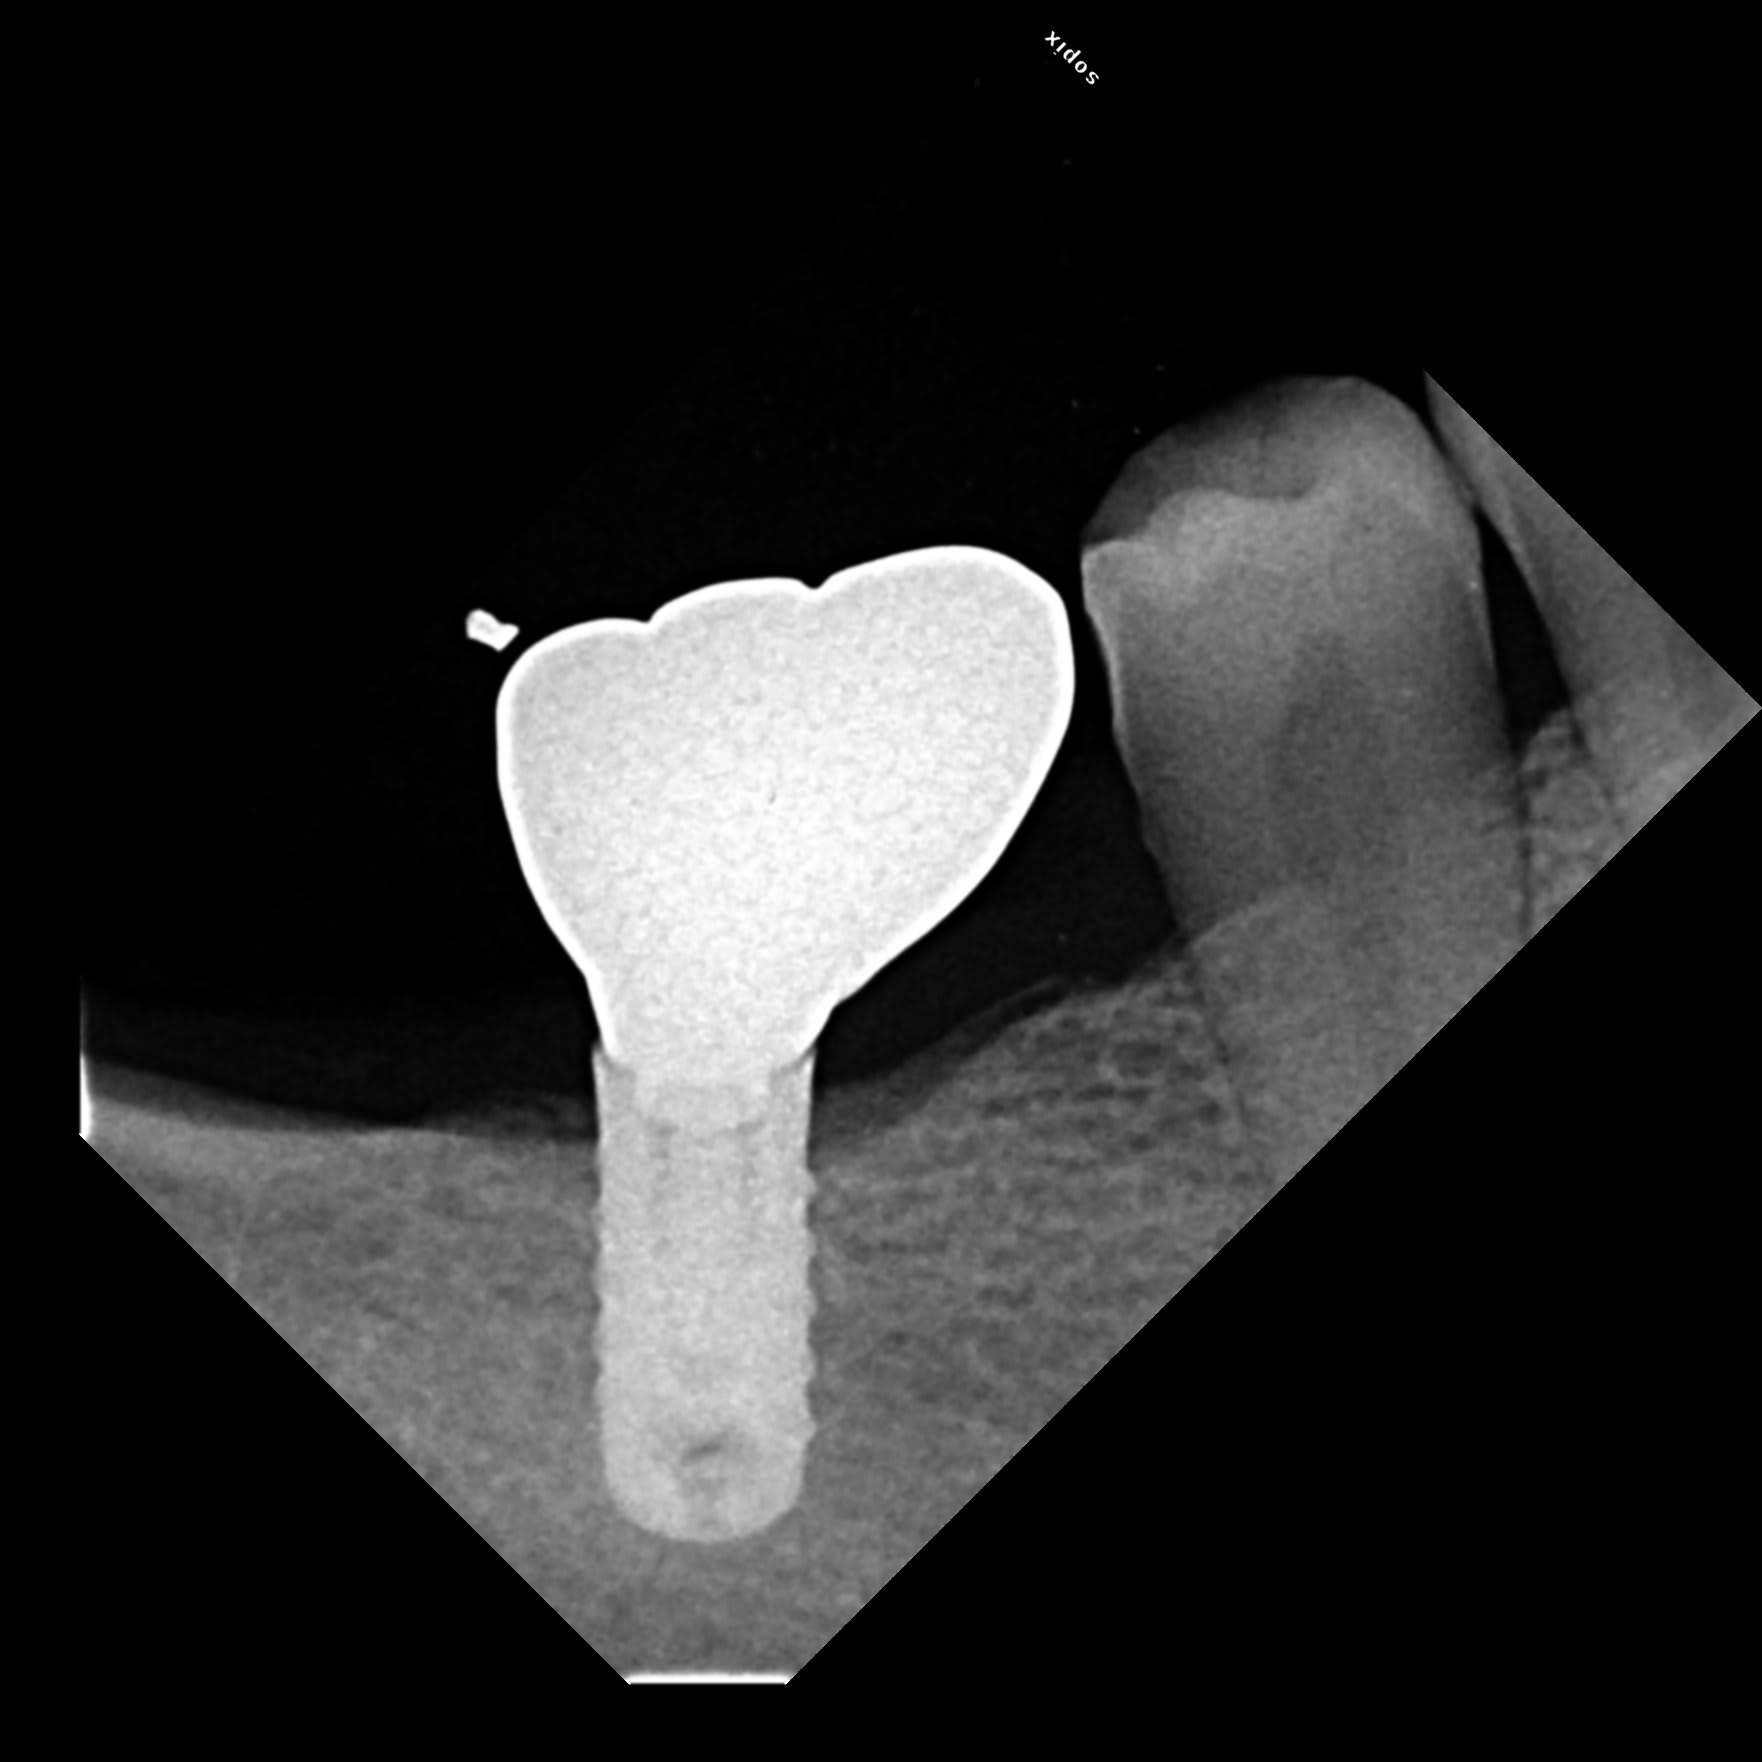

Voici un implant posé entre 2015/2018 à identifier .

pas top la photo au smartphone d'un zoom de pano....

on va dire identification à 80%....car je veux bien mettre une pièce sur un biotech kontact

http://osseosource.com/dental-implants/product_info.php?manufacturers_id=144&products_id=2524

je pense aussi.

Une image radio sur un cas avec un implant similaire.